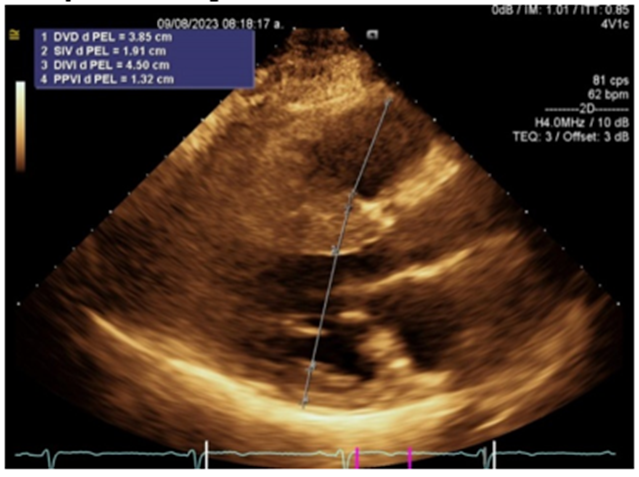

The first case, with a benign course and good prognosis, involved a 57-year-old female patient with a family history of hypertrophic heart disease, a 45-year-old sister being treated for heart failure, and healthy family members. The patient had cardiovascular risk factors characterized by a sedentary lifestyle, type 2 diabetes, and systemic arterial hypertension, both of which were at target levels with pharmacological treatment. The patient had a history of cardiovascular functional class decline for approximately 5 years. The reason for consultation was due to worsening of symptoms for approximately 6 months, upon questioning he was in NYHA functional class I, his primary physician performed a first approach with a chest x-ray and electrocardiogram where criteria for left ventricular hypertrophy and cardiomegaly grade III respectively were evident, he was referred to the cardiology of our unit where on physical examination we found the patient with rhythmic heart sounds of adequate intensity, without murmurs, with apex displaced to the anterior axillary region, a transthoracic echocardiogram was performed where non-obstructive asymmetric septal hypertrophic cardiomyopathy was documented without obstructive gradient (5mmHg), nor significant increase in it after the Valsalva maneuver, diastolic dysfunction with a restrictive pattern and increased filling pressures, the myocardium with a honeycomb image suggestive of an infiltrative pattern, the left ventricle with increased internal diameters and indexed volumes, with preserved systolic function of 61% by Simpson biplanar method. Due to family history, genetic screening was performed, finding a mutation in the tropomyosin 1 gene, variant c.841A>G;p. (Met281Val), classified as of uncertain significance, is associated with hypertrophic cardiomyopathy (OMIM: 115196), in addition to dilated cardiomyopathy and non-compact myocardium, all with a benign course, with autosomal dominant inheritance. Therefore, management was established with ACEI and Beta-blockers, with functional class monitoring, last assessment in December 2024 without functional class progression, currently without surgical criteria, continues without obstructive gradient.

Figure 2: Long parasternal axis showing increased basal septal thickness